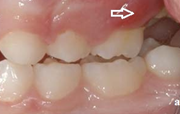

Esimeste molaaride (purihammaste) lõikumine

Esimeste molaaride (purihammaste) lõikumine. 1. molaaride ektoopilise lõikumise jälgimine. Ülemised ja alumised esimesed purihambad e. molaarid lõikuvad orienteeruvalt6-7-aastaselt piimahammaste rea lõppu. Enamasti lõikuvad samanimelised jäävhambad paaridena. Normaalne lõikumise Loe edasi »

Sümptomid:

- valehambumus (18)